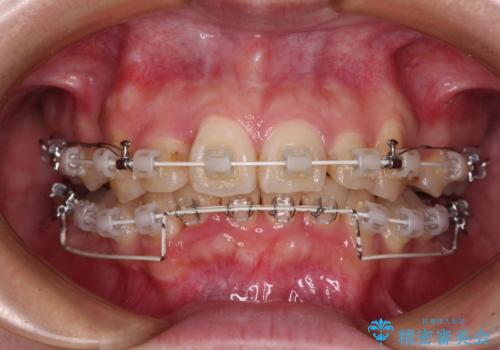

- 審美装置

上下の前歯にデコボコがあり、更にはディープバイトにより下顎前歯の大半が隠れている状態でした。

上顎左右第一小臼歯の2本を抜歯し、ワイヤー装置を使用して咬み合わせ高さを改善しながら、歯列を整えて行くこととしました。